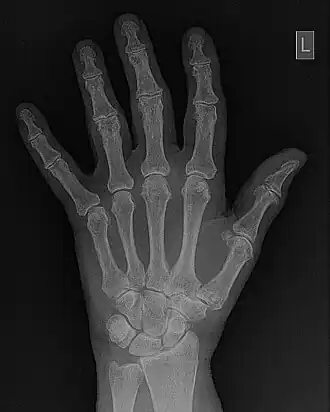

- Fourier filtering is illustrated in more detail in Figure 5.10. The wrist/hand radiograph of the Figure 5.6 is again used for this illustration. You might remember that its 2D FFT was discussed in an earlier chapter. The filter is shown in panel (c) of the figure in the form of a two-dimensional image. It can be seen that the image data is symmetrical around the centre (i.e.isotropic) where its pixel values are relatively low. Outside this central dark region, a halo of bright pixel values dominates the image as the pixel value trails off slowly towards the periphery. An amplitude profile through this image is shown in panel (d) to further illustrate the effect. The filter can be used to modify the 2D-FFT by multiplying it by the filter values, for instance, to form a filtered 2D-FFT - as shown in panel (e). The Inverse FFT (IFT) of this data is then reveals the filtered image - see panel (f). Given that certain spatial frequencies have been amplified while others have been suppressed with this type of filter, it is called a Bandpass filter.